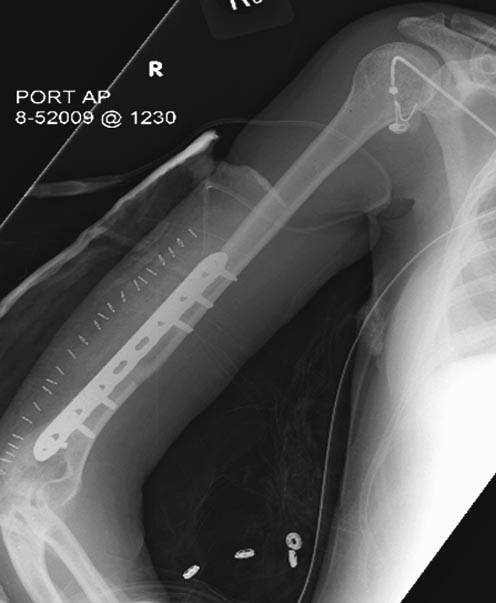

Раны в области коленного сустава и на плече до сих пор чистые, остаются открытыми. Отсутствует признаки инфекции, решили превратить недостаток в преимущество, т.е. фиксировать через открытые раны пластинами.

На 11й день фиксация плеча также пластиной.

На 25 день с момента травмы операция на Jackson table с боковым обширным доступом. Удаление стержней с местной обработкой. В тазобедренном суставе удаление головки, на дне вертлужной впадины полная отслойка хряща. Вертлужный компонент с одним винтом и короткая ножка - Fitmore press fit stem. На второй день однократно доза радиации для профилактики гетеретопической оссификации. Послеоперационный период без температуры. Выписана. Нагрузку разрешили на левой стороне, а полная в 3 мес. Здесь снимки при амбулаторном наблюдении: послеоперационно, 2 мес, 3 мес и 6 мес. Нагрузка полная, отсутствует хромота, и нет жалоб.